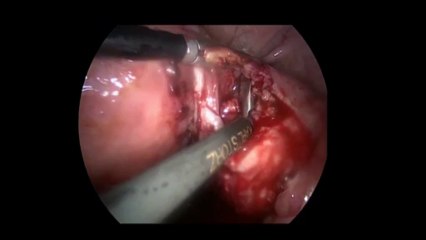

Laparoskopi ile Endometiroma (Çikolata kisti) operasyonu 1 - Prof. Dr. Aydan Biri

Laparoskopi ile Endometiroma (Çikolata kisti) operasyonu 1 - Prof. Dr.